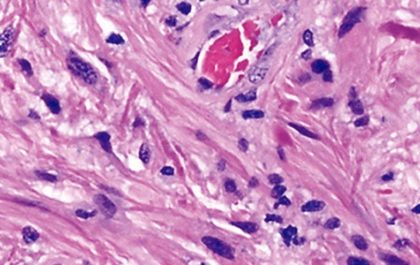

Portrait of a Tumor

A new DNA methylation profiling tool that ensures brain tumors are accurately diagnosed is available at Northwestern Medicine.